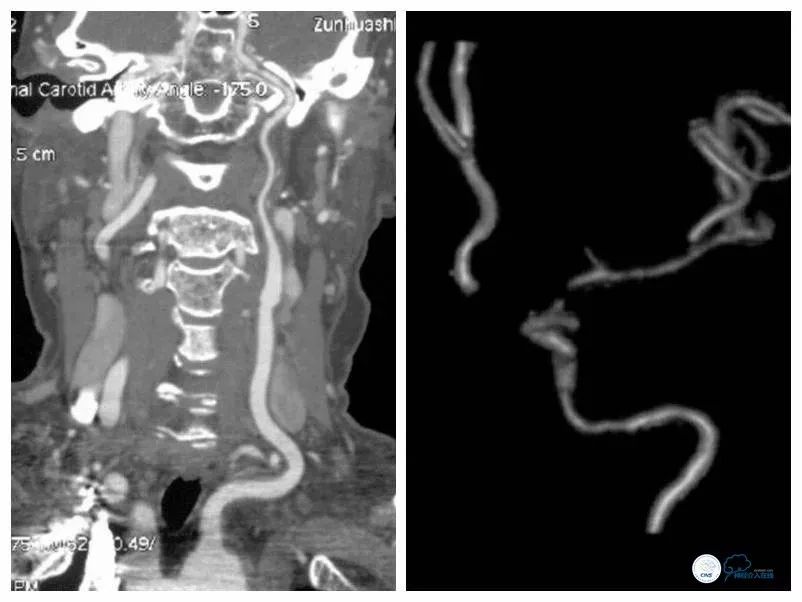

颅内及弓上CTA(2018-4-19):左颈内动脉末端、大脑中动脉起始部重度狭窄(图2)。

图2